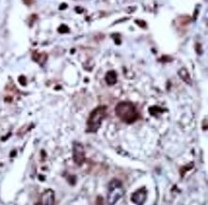

ARG55448 anti-STK39 / SPAK antibody IHC-P image

Immunohistochemistry: Formalin-fixed and paraffin-embedded Human cancer tissue stained with ARG55448 anti-STK39 / SPAK antibody.